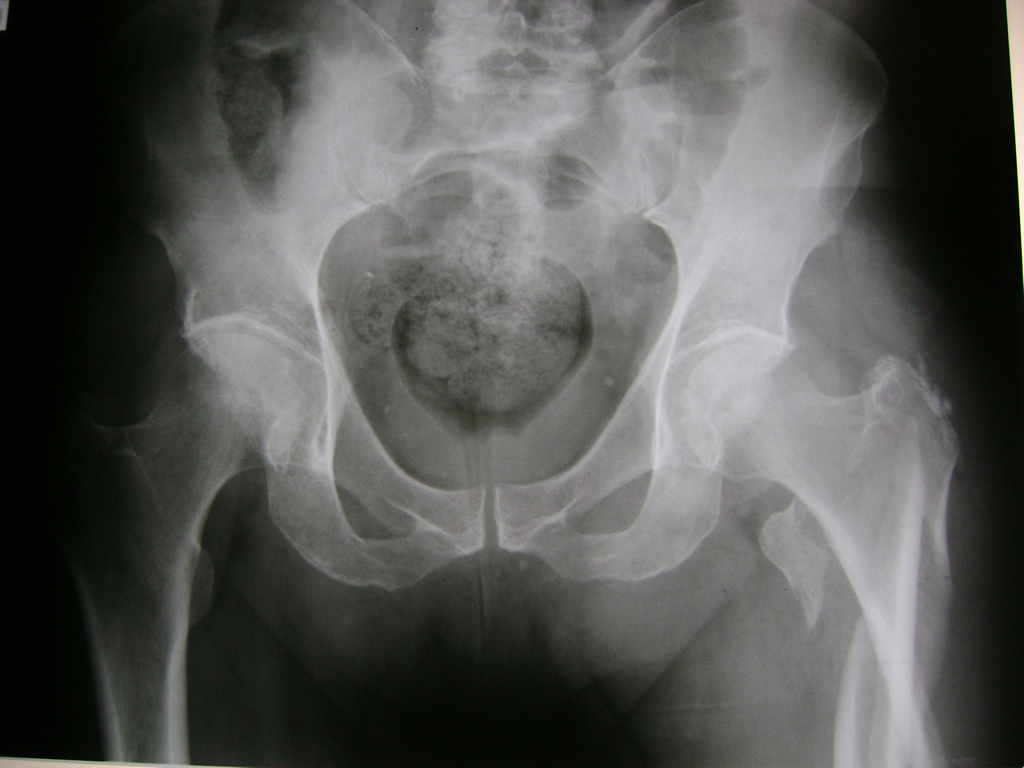

La cirugía de fractura de cadera se realiza para reparar una ruptura en la parte superior del hueso del muslo. Este hueso se denomina fémur.

Es parte de la articulación coxofemoral. Si una fractura de cadera no recibe tratamiento, es posible que deba permanecer en una silla o en la cama.

A menudo se recomienda la cirugía para reparar la fractura debido a dichos riesgos.